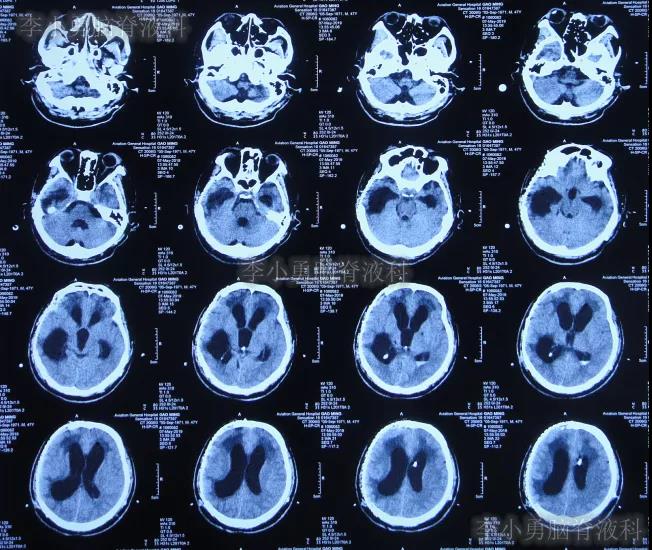

2019年4月2日(第4家医院治疗192天即脑室腹壁外引流术后176天),按计划进行钛网颅骨修补术,术后当天查头颅CT示颅骨修补术后(图-3)。

图-3:2019年4月2日头颅CT

入院治疗69天即2020年3月27日,进行了脑室腹腔分流术(图-14)。

图-14:2020年3月27日脑室腹腔分流术后

入院治疗88天即2020年4月15日出院,出院时:病情好转为,意识变清,肢体能遵嘱活动,变得能坐轮椅活动,比入院时体重明显增加(图-15);出院时头颅CT示未见异常(图-16)。

图-16:头颅CT出院时